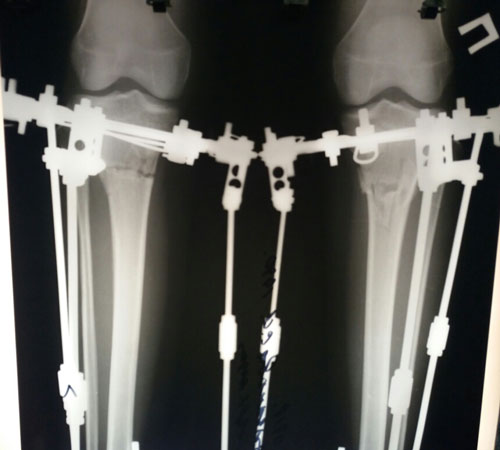

Дата операции 06.02.2018г.

Дата снтия аппаратов 02.05.2018г.

Срок лечения 86 дней.

Как мастерски исправлена такая страшная Ротация!

На сращении